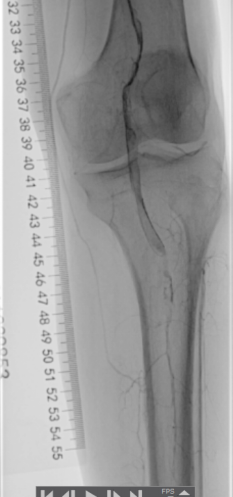

术前下肢动脉CTA提示:左下肢股、腘动脉长段闭塞,膝下动脉主干未见显影,可见少量侧支血流。

血管外科姜坤主任团队仔细分析患者病情,该患者在动脉硬化闭塞基础上继发血栓形成,且血栓负荷量大,身体状况差,行麻醉及开放手术取栓的风险大,遂制定了微创腔内的手术方案,采用动脉机械血栓清除+血管成形术。

术中选用Rotarex导管行血栓清除,对管腔内残留的血栓放置溶栓导管,最后采用球囊扩张狭窄病变,管腔获得满意。